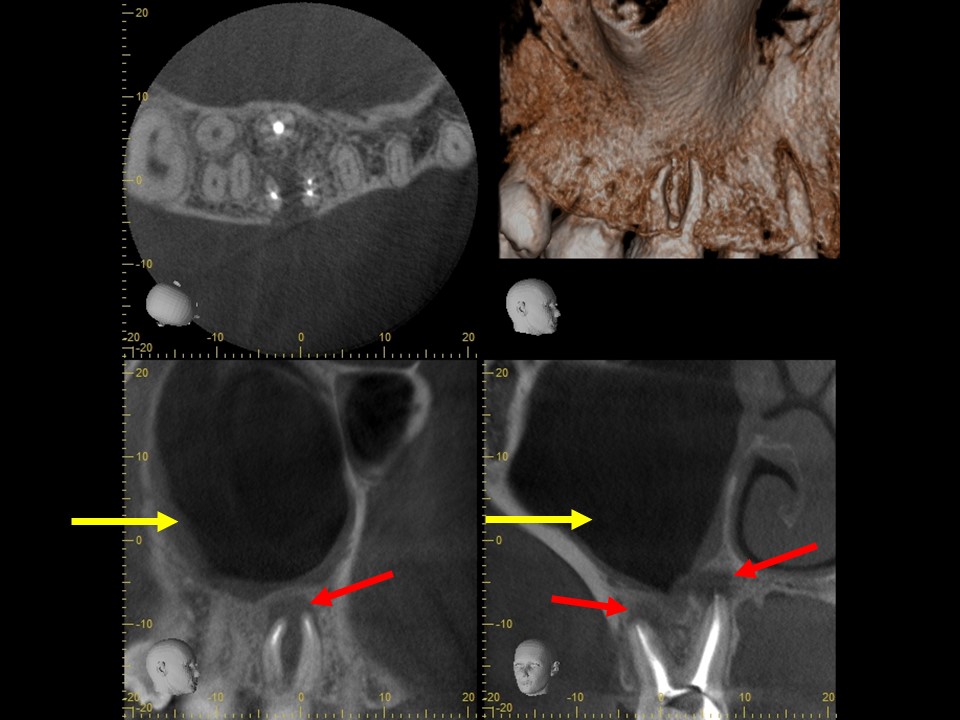

右上の6番の大臼歯に、大きなコンポジットレジン充填がしてありました。レントゲンおよびCT診査を行ったところ、歯髄に達する大きな充填の跡が見られ、根尖部の骨はすでに大きく溶けて吸収しており、炎症は副鼻腔に達していました(下写真)。レントゲンおよびCT画像から、虫歯治療後の歯髄壊死・壊疽から生じた慢性化膿性根尖性歯周炎と診断しました。また、根尖病変に起因する歯性上顎洞を併発していると診断しました。

治療前のレントゲンおよびCT画像です。右上6番には歯髄に達する大きなコンポジットレジン充填がされています。

根尖部の骨は黒く大きく溶け(赤矢印)、ほぼ上顎洞と交通しています。

上顎洞内部は上方までX線不透過性が亢進し(白くなっています)、典型的な上顎洞炎の像を呈しています(黄矢印)。

根管充填3か月後のCT画像です。根尖病巣は顕著に縮小しており、骨の再生を認めます(赤矢印)。上顎洞の炎症も消退し、ほぼ正常像を呈していることが分かります(黄矢印)。病状が治癒傾向を認めるため、歯冠修復処置を行っていきます。

根管治療14か月後のレントゲンおよびCT画像です。術前にあった根尖部のX線透過像(赤矢印)ならびに上顎洞内のX線不透過性の亢進(黄矢印)は完全に消失し、根尖病変および歯性上顎洞炎は良好に治癒しているのが確認できます。